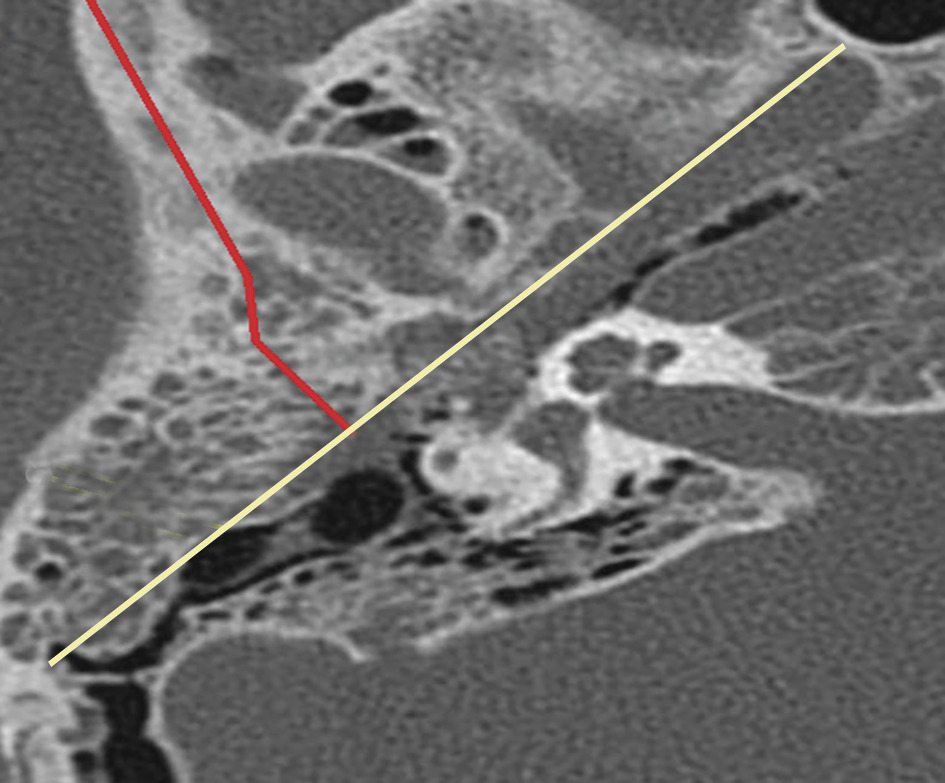

La classification anatomopathologique différencie les fractures longitudinales, plus fréquentes (parallèles à l’axe de la pyramide pétreuse, secondaires à un choc latéral temporopariétal homolatéral), les transversales (perpendiculaires à l’axe du rocher, post-impact frontal ou occipital) et les mixtes (mélange des 2 types précédents ;figure ).1

La classification anatomopathologique différencie les fractures longitudinales, plus fréquentes (parallèles à l’axe de la pyramide pétreuse, secondaires à un choc latéral temporopariétal homolatéral), les transversales (perpendiculaires à l’axe du rocher, post-impact frontal ou occipital) et les mixtes (mélange des 2 types précédents ;